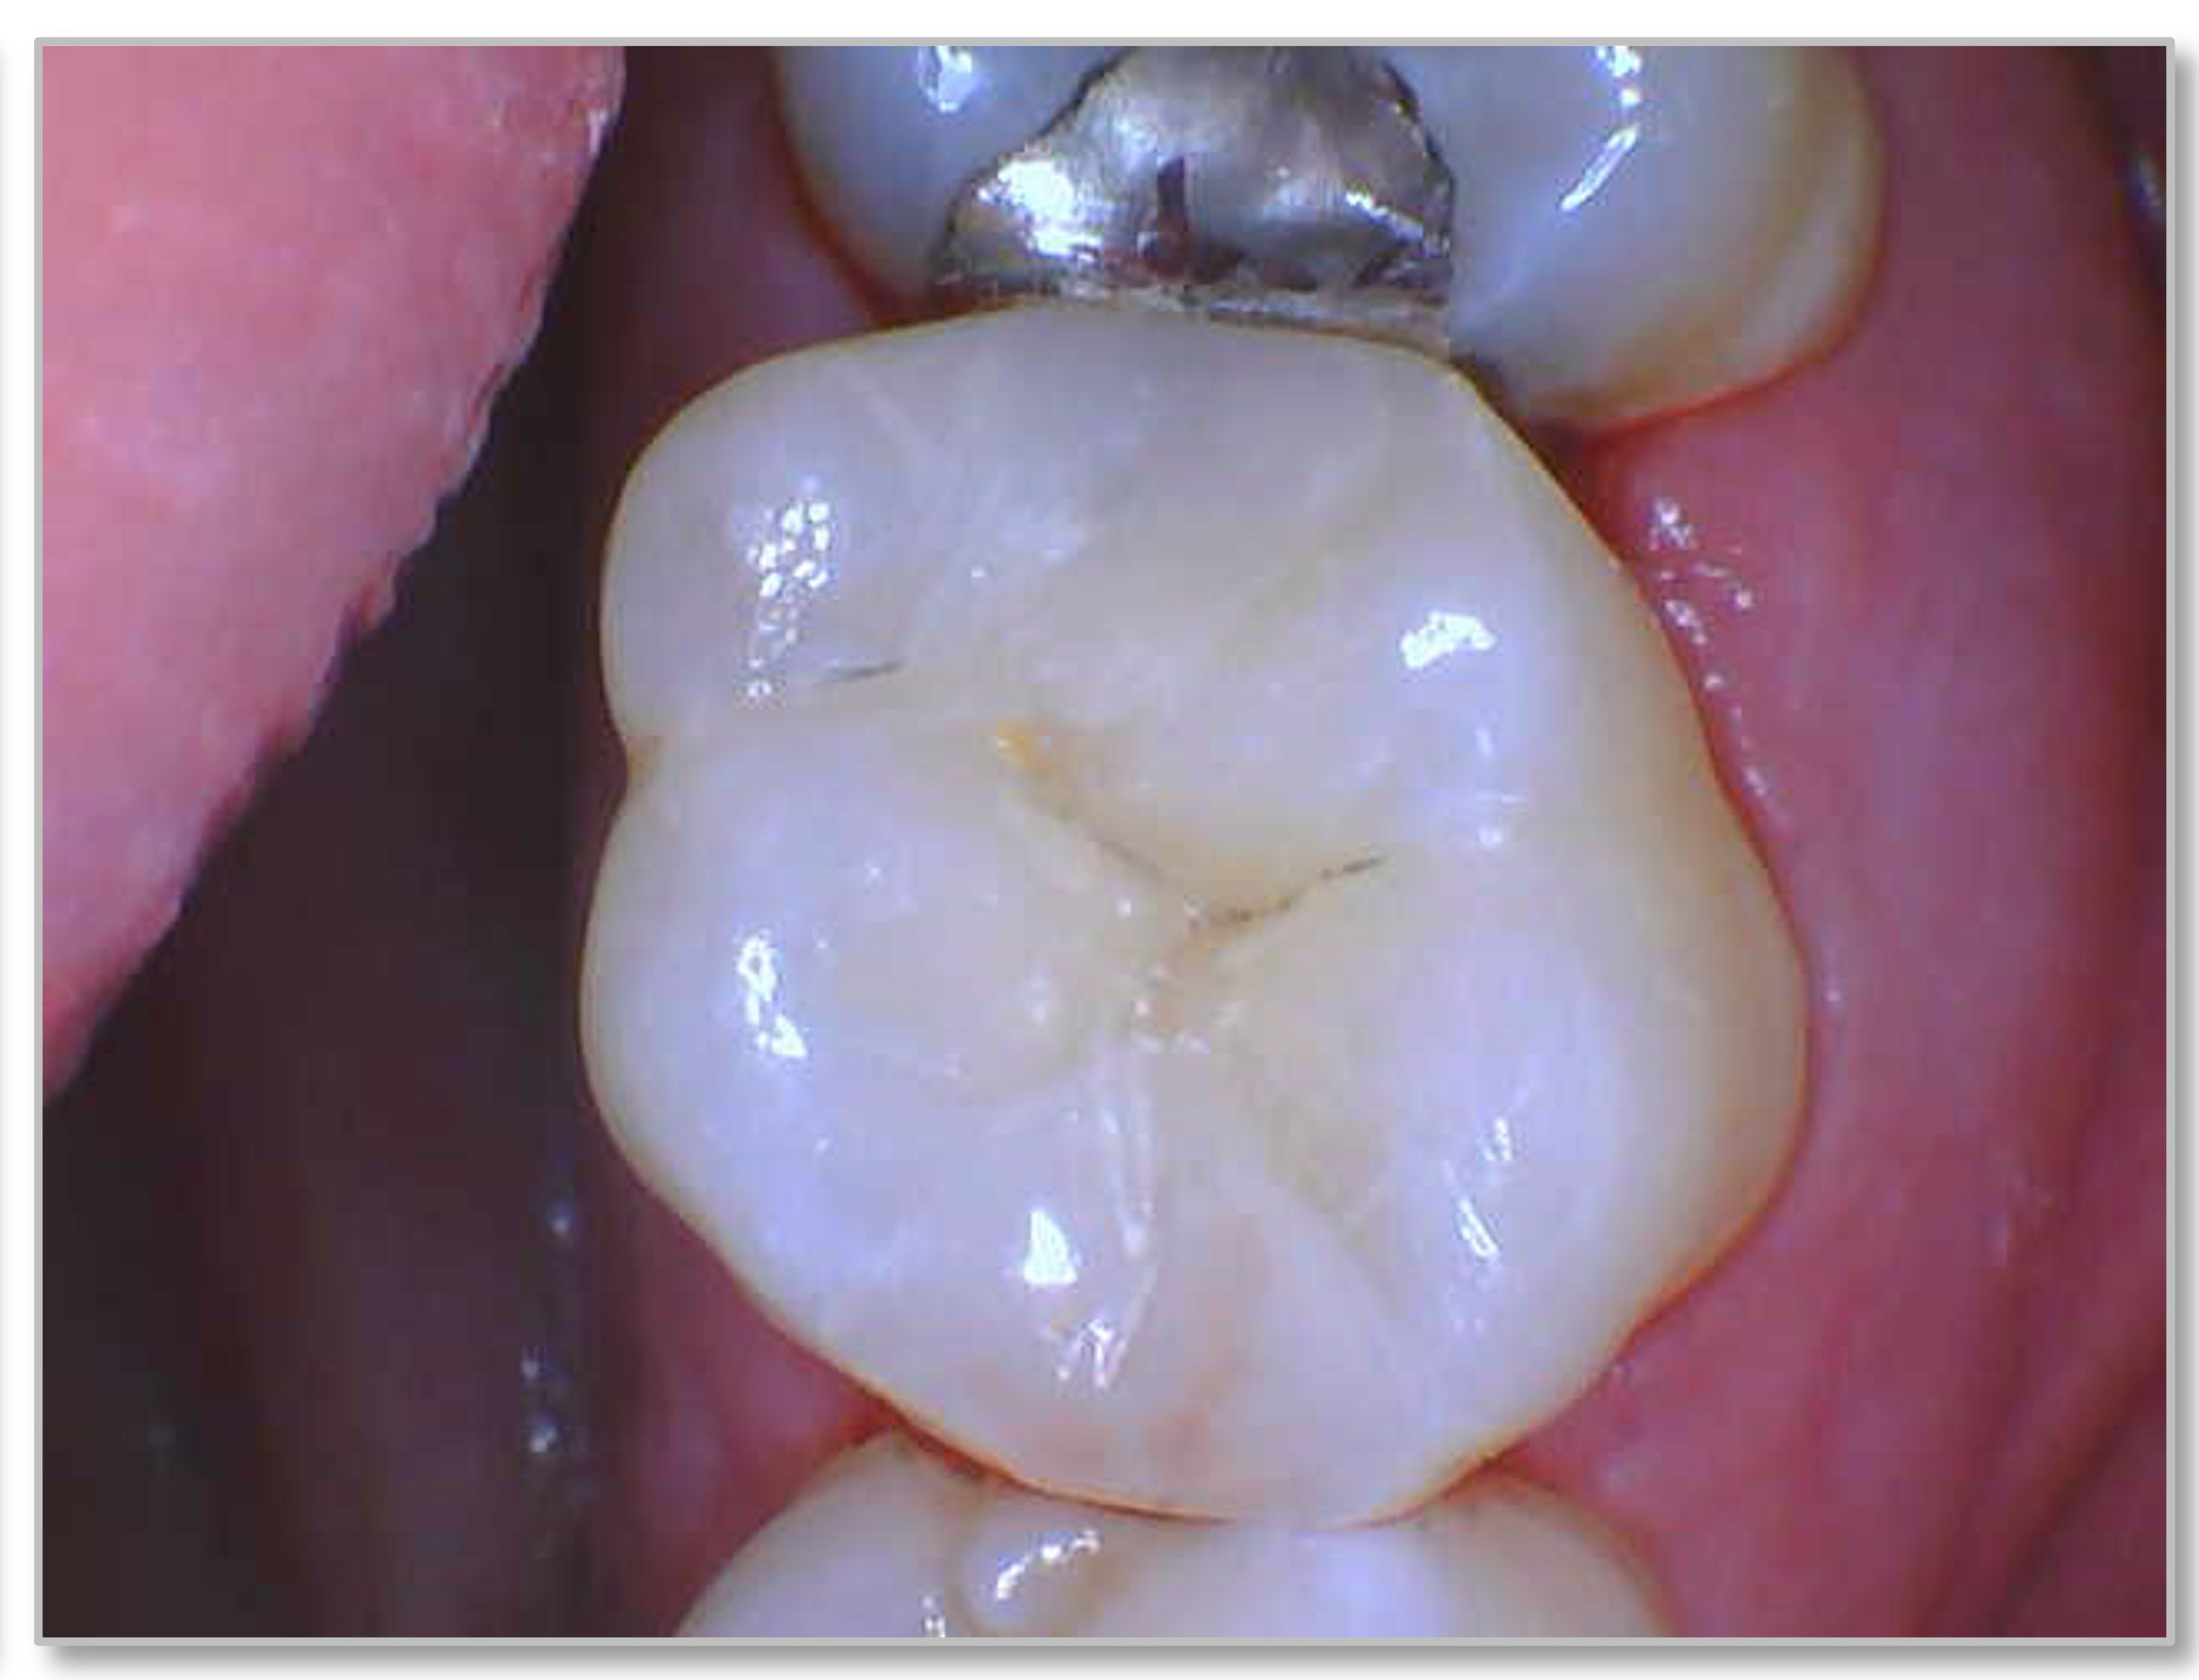

Figure 3a and Figure 3b show a failing composite with stress fractures and interproximal decay. The patient was not in a situation to do an indirect restoration, so the practitioner did a direct composite with good strength and wear characteristics until an indirect restoration could be performed. The composite used in this case is the Kerr SimpliShade Bulk Fill Packable, which in the author's experience also offers good blendability and polishability with good adaptation. Some of the discoloration interproximally is from the bleeding after the rubber dam was removed-which quickly self-resolved.

Fig 3b. A direct composite using Kerr SimpliShade Bulk Fill Packable.

Fig 3b.